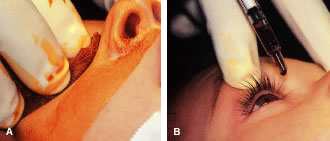

The eyelids and surrounding skin are prepared with two scrubs using a 10% povidone iodine (Betadine) solution that is diluted 50:50 with warm saline38–41 (Fig. 3A and B). The conjunctival cul-de-sacs are irrigated with a bulb syringe and warm saline. Silver protein precipitating solutions, such as Argyrol are not used. A drop of 1% phenylephrine hydrochloride may be instilled into the conjunctival cul-de-sacs to reduce conjunctival bleeding (Fig. 4). The surgical field is isolated with a sterile adhesive barrier drape (see Fig. 4 and Fig. 5). The instrument tray is positioned, and sterile cotton-tipped applicators are placed on either side of the head so that they are available for sponging the field (Fig. 6). A wet-field or bipolar cautery is available. The surgeon is seated at the head of the operating table. The assistant sits to the left of the surgeon, and the surgical technician sits to the right (Fig. 7). Consistency in the procedures that are used to prepare a patient for surgery, such as positioning of the patient and location of the surgeon and the assistants, helps to eliminate confusion among the operating room staff before each procedure. Surgical instruments can be placed on a Mayo stand if a surgical technician is not available to pass instruments to the surgeon (see Fig. 6). The clinical record is positioned where the surgeon can refer to it.